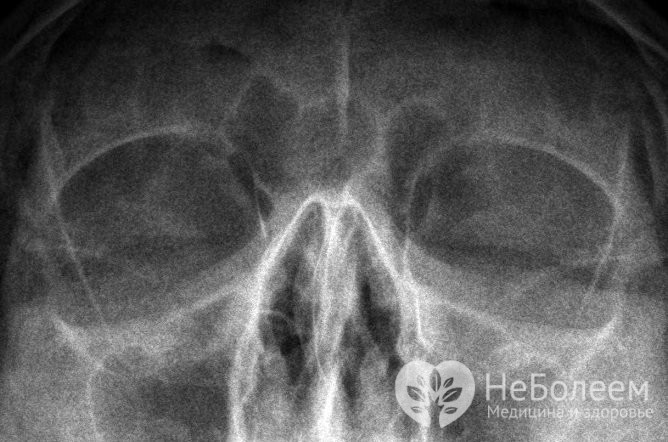

- рентгенографія носових пазух – призначається при підозрі на синусит;

Вазомоторний риніт диференціюють з алергійним нежитем, синуситом, туберкульоз, склеромой, сифілісом і гранулематозом Вегенера. Для уточнення діагнозу зазвичай призначають рентгенографію придаткових пазух, загальний аналіз крові та алергологічні проби.

Щоб диференціювати вазомоторний риніт з іншими патологіями ЛОР-органів, проводять рентгенографію придаткових пазух носаЗа показаннями проводяться додаткові дослідження – ринопневмометрия і ендоскопічне дослідження носової порожнини, мікроскопія зразків епітелію слизових оболонок і бакпосів слизових виділень з носа.